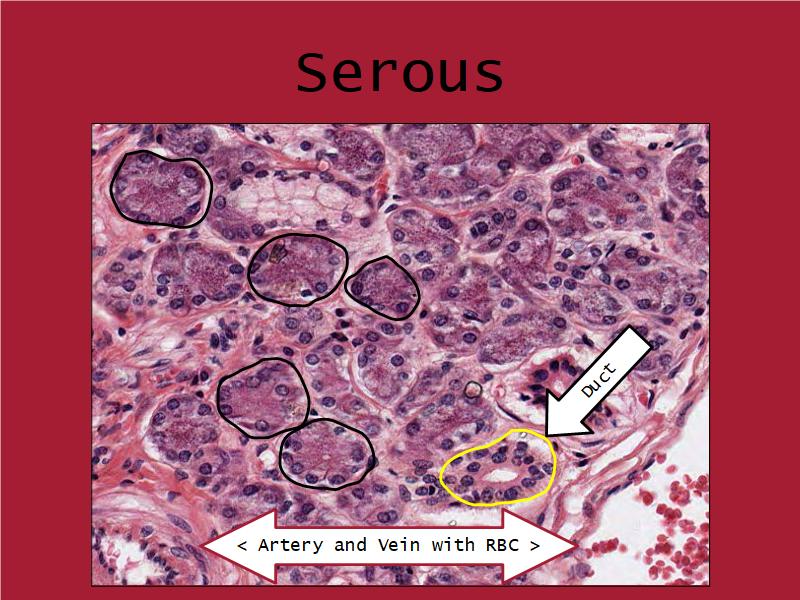

Cancer Association of South Africa (CANSA):Q03 - 1

List 2 types of exocrine secretions:

- Serous

- Mucinous

Mucinous and serous secretory units from the Virtual Microscopy Database at http://virtualmicroscopydatabase.org/

Title: Salivary Gland, Sublingual, Human

Title: Submandibular Gland

Owner: H Goldman

Drexel University - Collection Gastrointestinal System

Used under the BY-SA-NC Creative Commons License